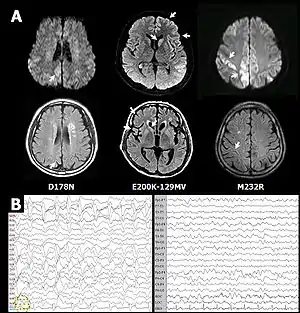

Попередній діагноз хвороби Кройцфельда-Якоба можна встановити (при наявності характерних симптомів) за допомогою електроенцефалограми (ЕЕГ). На ЕЕГ в разі хвороби Кройцфельда-Якоба характерна поява трифазної активності, рання пароксизмальна активність зазвичай діагностується через 12 тижнів і більше від дебюту спорадичної форми. Фокальна, билатеральна і генералізована міоклонічна пароксизмальна активність діагностується на продромальній, початковій і термінальній стадіях хвороби Кройцфельда-Якоба відповідно. Можуть реєструватися різні види періодичної пароксизмальної активності: двофазні або трифазні періодичні комплекси, що виникають кожні 1-2 с; періодичні комплекси з мультіфазною конфігурацією; періодичні поліспайкові розряди. ЕЕГ-патерн («спалах-пригнічення») характерний для термінальної стадії захворювання з явищами глибокої атрофії кори.